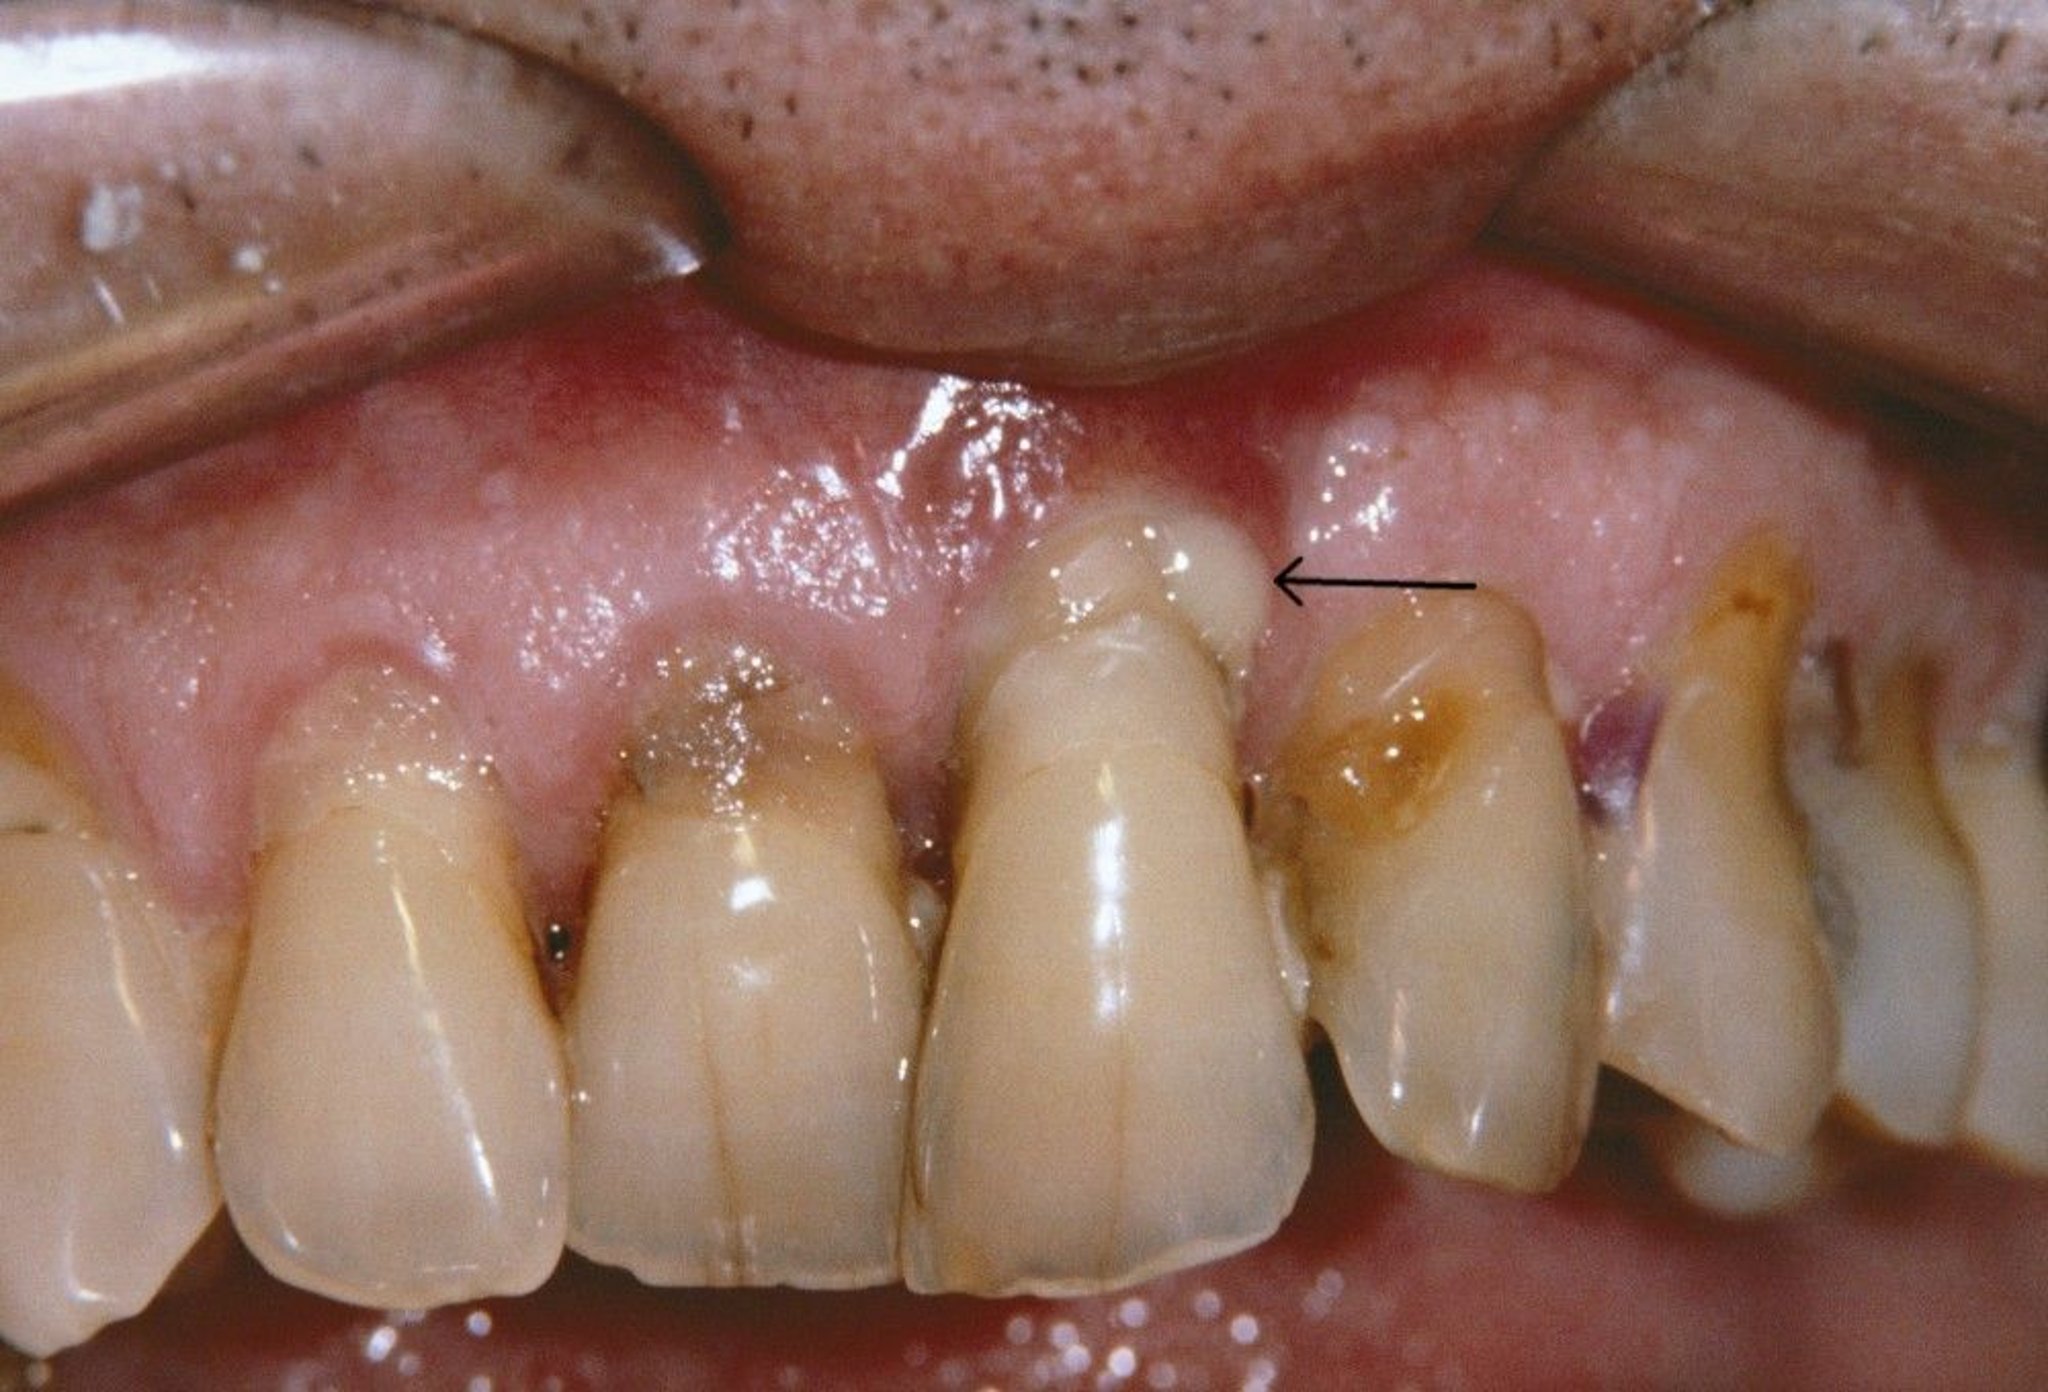

Picha hii inaonyesha ufizi unaolegea na jipu la periodintis (mshale) kwa mtu ambaye ana ugonjwa wa periodontitis.